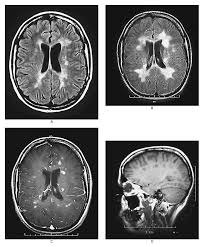

El organismo de las personas con esclerosis múltiple va destruyendo poco a poco la mielina, es decir, la sustancia que recubre los nervios, y eso hace que la transmisión de señales nerviosas se vea deteriorada y aparezcan síntomas como espasmos musculares, problemas en la coordinación o temblores, entre otros muchos. Ahora un equipo formado por varios centros europeos de Alemania y Suiza y por la Universidad Northwestern (Chicago) ha desarrollado una terapia que, a modo de vacuna, consigue engañar al sistema inmune, el principal enemigo de la mielina y frenar su deterioro. De momento, se trata de un estudio realizado con nueve pacientes que sólo demuestra que este tratamiento es seguro y bien tolerado por el cuerpo humano. Pero abre la puerta a una nueva forma de tratar esta enfermedad.